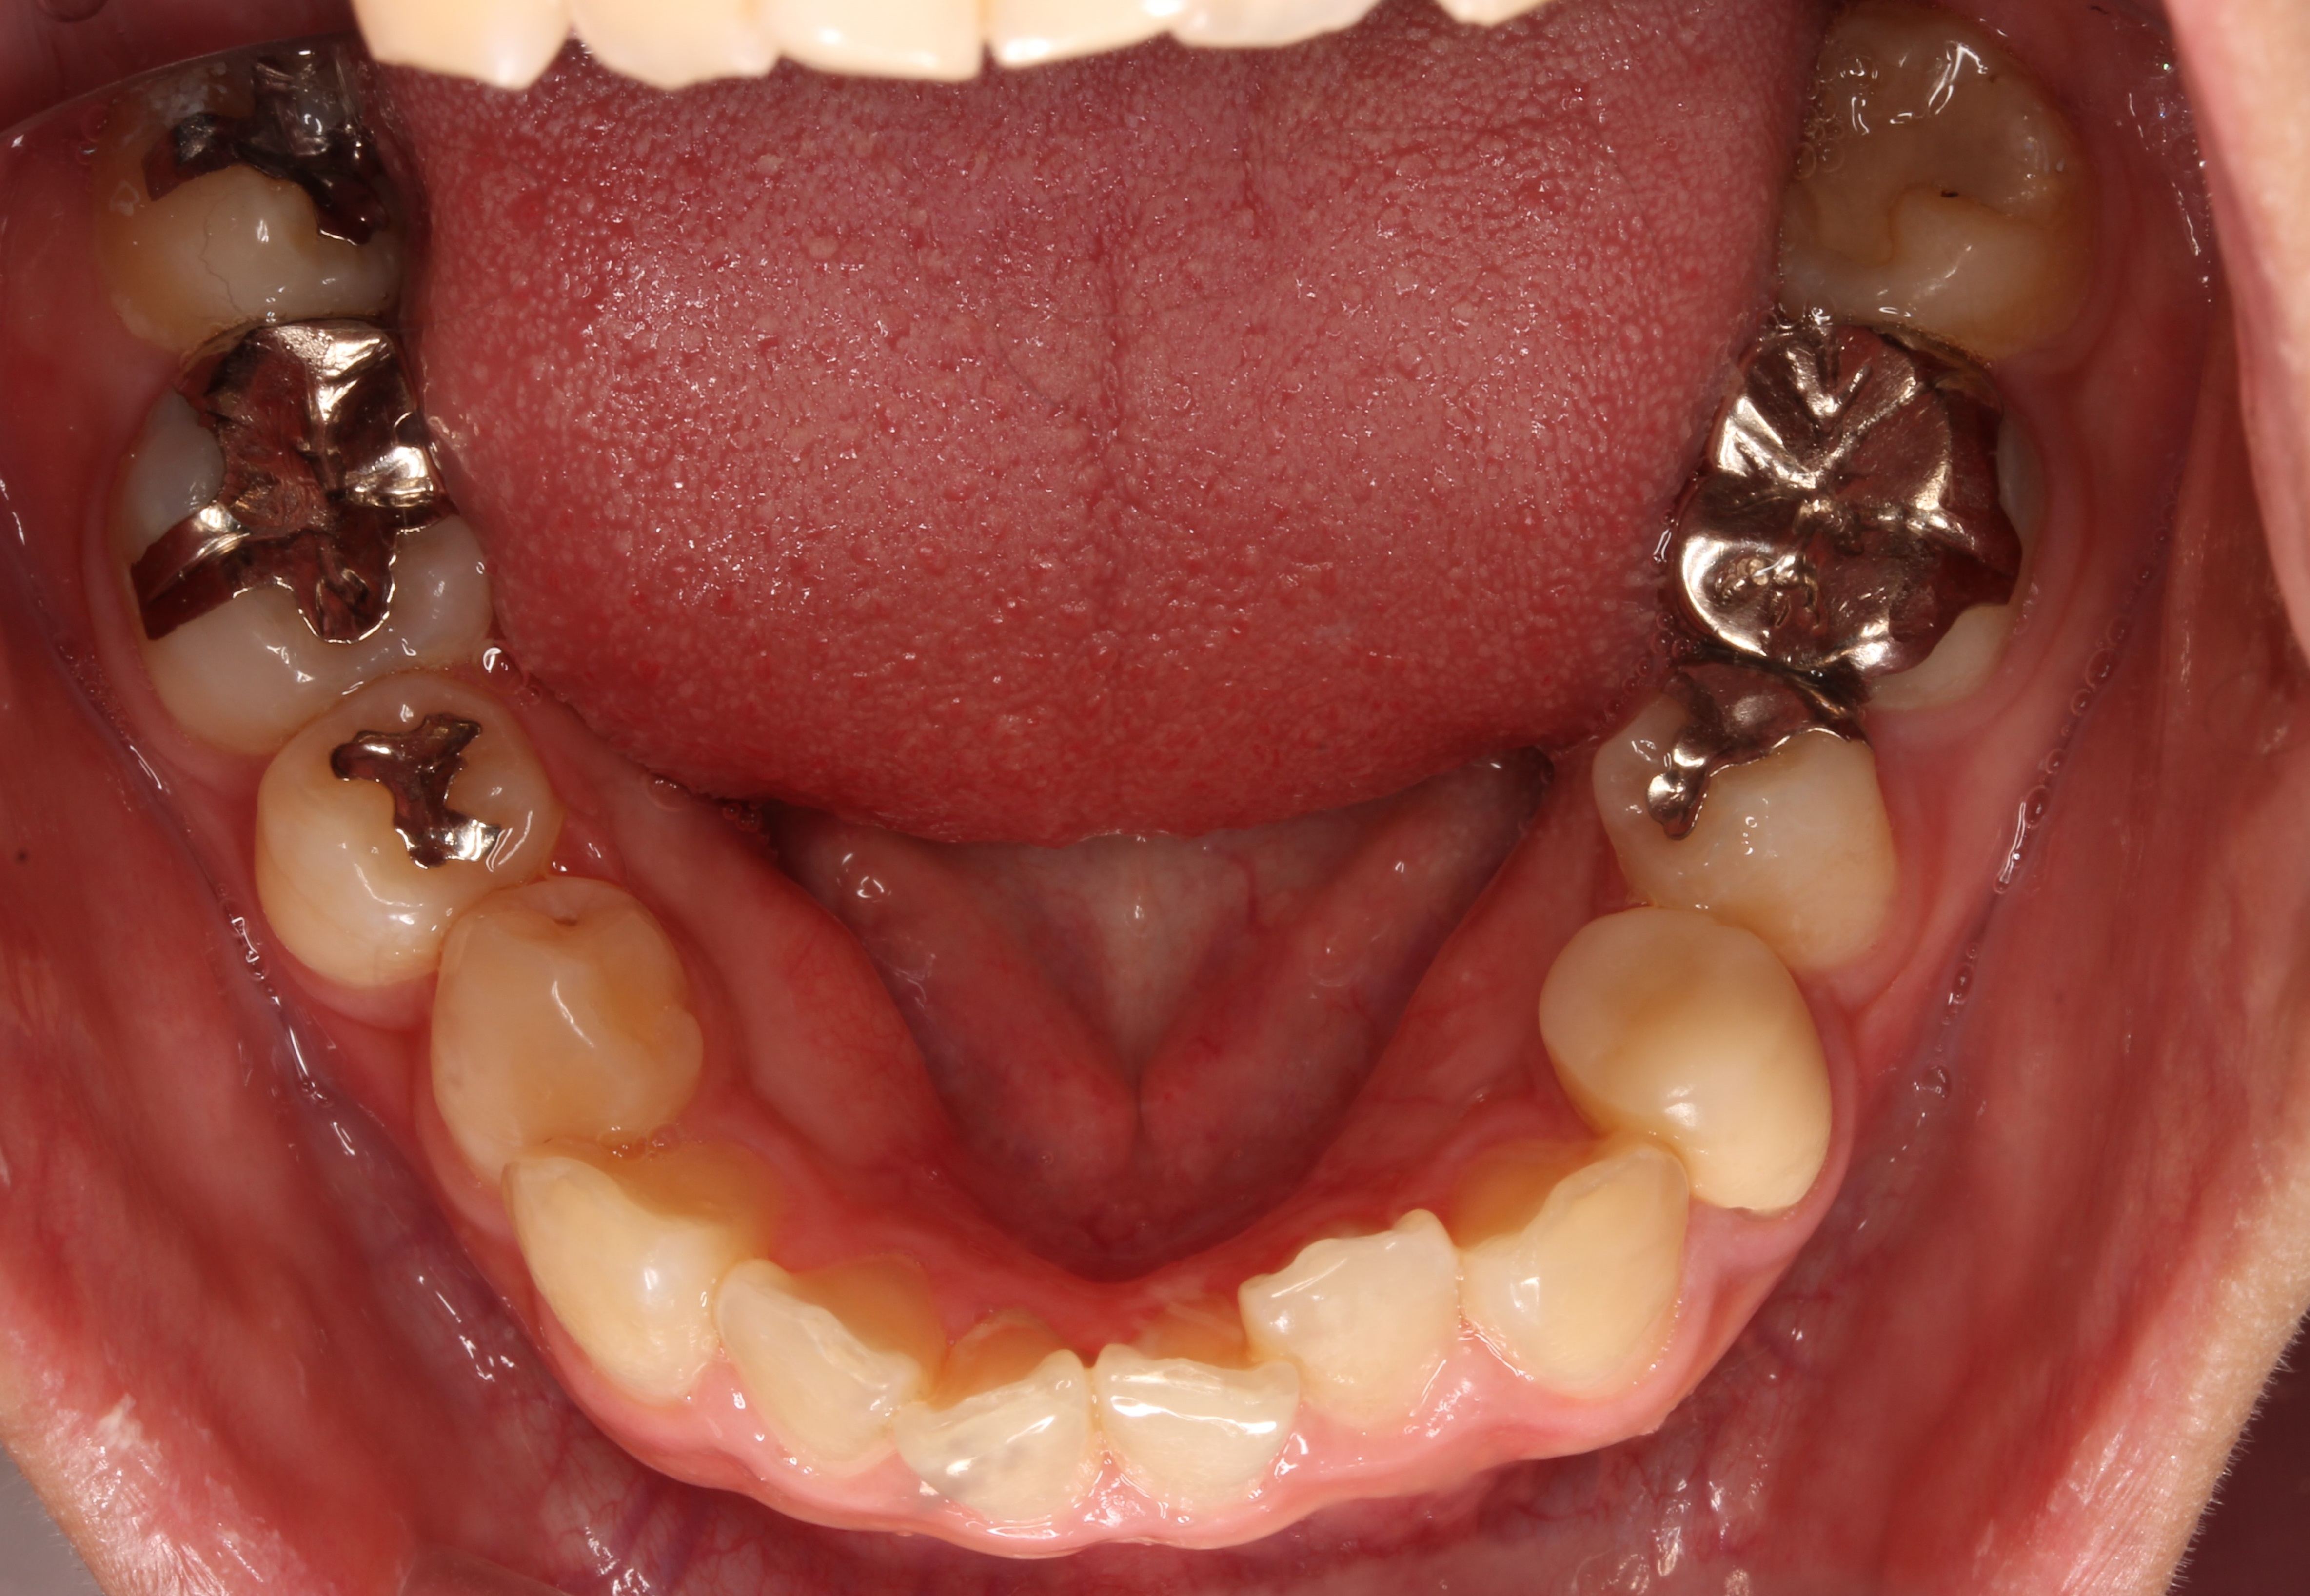

術前写真です。

下の歯には、5本の銀歯が入っていました。